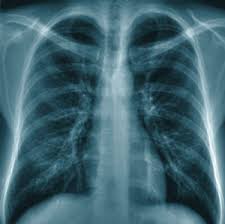

Poumons d'un non fumeur est de couleur blanc et se gonfle normalement , elle contient plus d'alvéole pulmonaires. Les bronches du fumeur, ou d'un ancien fumeur, sont généralement encrassées par les années d'exposition à la fumée du tabac. Par contre, les poumons d'un fumeur sont noircis par le goudron du tabac, leurs formes diminuent et étant obstrués, ils ne jouent plus leur rôle;

Une Infirmiere Montre Les Poumons Tout Noirs D Un Fumeur Midilibre Fr

visitez l'article complet ici : https://www.midilibre.fr/2018/05/04/une-infirmiere-montre-les-poumons-tout-noirs-d-un-fumeur,1665980.php